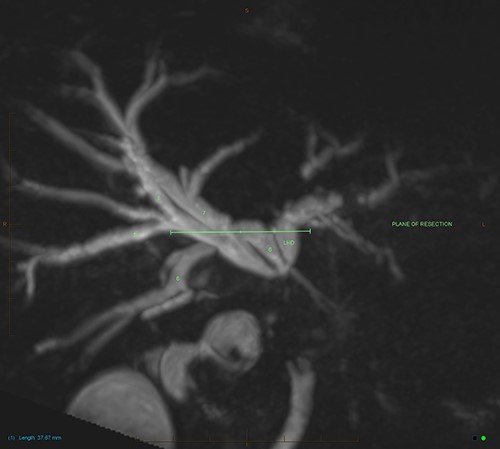

MIP reconstruction of 3D MRCP reveals abrupt segmental stricture of the common hepatic duct with marked intrahepatic biliary dilation. Trifurcation of the biliary confluence into the left hepatic duct, aberrant segment 6 duct and the right hepatic duct. The right hepatic duct is formed by the union of right anterior (segment 5,8) duct and segment 7 duct while the segment 6 duct is joining separately at the confluence. The approximate plane of surgical resection is indicated.

The patient underwent an open pancreaticoduodenectomy and cholecystectomy. Surgical resection was extended proximally to include the biliary confluence and biliary transection was performed to reveal four separate bile duct openings consisting of the right anterior and posterior sectoral ducts, a separate segment 6 duct and the left hepatic duct (Fig. 4).